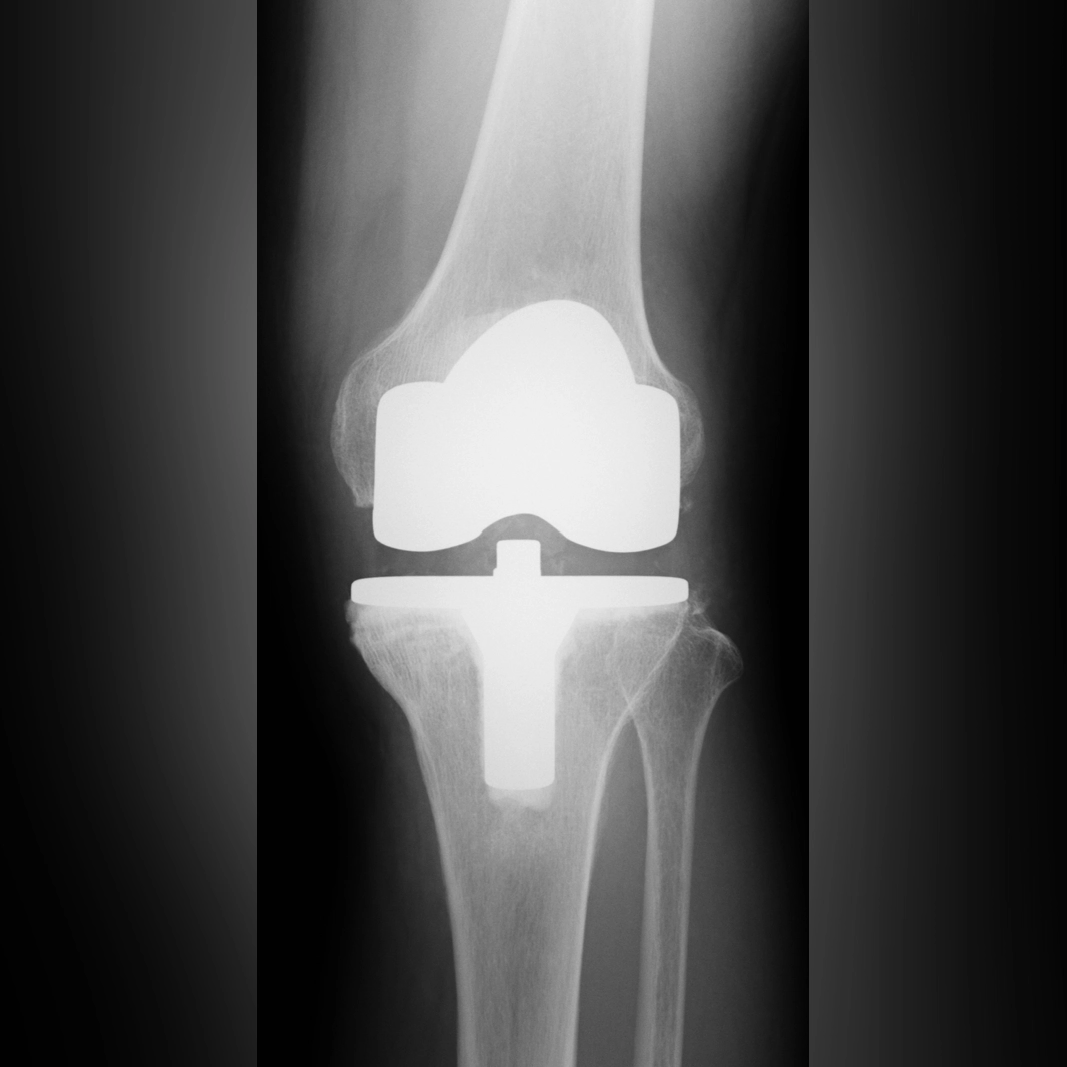

全置換術(TKA)

まず、日本で変形性膝関節症の手術といえば、全置換術(TKA)が挙げられます。ひざ関節のすべてを金属に置き換え、その間に人工の軟骨を挿入することで、レントゲン上では隙間が見えるようになります。これによって骨同士がぶつからなくなり、痛みは解消されます。私が考えるこの手術の欠点は2つあります。1つは、関節の真ん中にある十字じん帯を切除してしまうこと。もう1つは、術後の腫れが強く、術前よりもひざの可動域が狭くなる方が多いことです。十字じん帯にはその緊張を脳へ伝える神経があり、これを切ることで“自然な動きの感覚”が失われます。